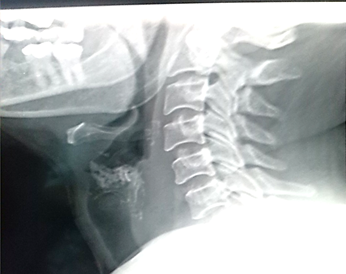

Pruebas de laboratorio: se aprecia leucocitosis en 12.000cel/mm3 y luego progresa a 24.500cel/mm3, polimorfo nuclear 90%, valores de glucosa en sangre elevada. Se le realiza rayos x de cuello (Figura 2. Anexos), y ecosonograma de región cervical, donde se describe una lesión ocupante de espacio alrededor de la tráquea hacia el lado izquierdo, de 4x 2 cm, heterogénea de bordes bien circunscritos. No presenta vascularidad al uso del Doppler. El lóbulo izquierdo del tiroides, muestra efecto de masa en su cara inferior. Concluye con una lesión ocupante de espacio en región traqueal izquierda sugerente de absceso frio. Se le realiza estudio de tomografía computarizada de cuello (Figura. 3, 4, 5. Anexos), y tórax, apreciando en región lateral izquierda del cuello, hiperdensidad paralela a la tráquea y glándula tiroidea, haciendo efecto de masa compresiva sobre las estructuras cercanas.

IMG_20181018_153522

Figura 2. Rayos x de región cervical en proyección lateral izquierda, no se evidencian hallazgos patológicos asociados a la lesión.

Fuente: Fotografía realizada por Dra. María Pulgar.